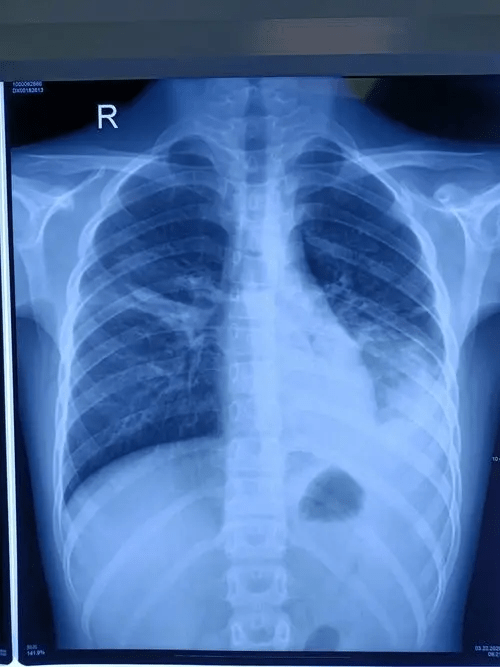

▲有患者染病后肺部变白。微博